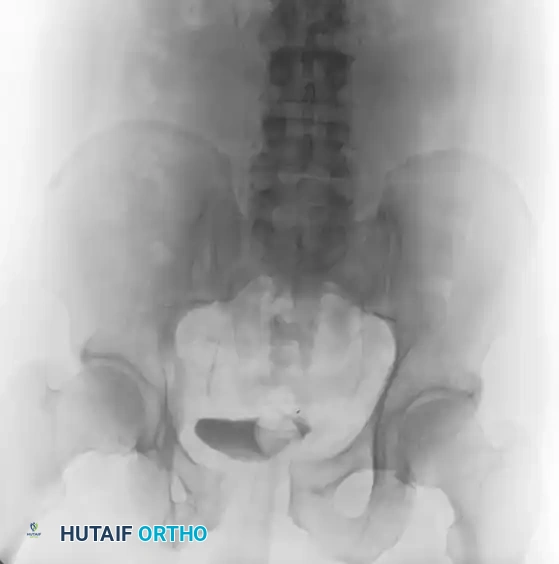

Case 2: Young-Burgess Lateral Compression Type II (LC II)

An LC II injury results from a lateral force vector. It is characterized by anterior transverse pubic rami fractures combined with a posterior iliac wing fracture (often a "crescent fracture" involving the posterior ilium extending into the SI joint). The hemipelvis is internally rotated.

Preoperative Evaluation:

The standard trauma series (AP, oblique, inlet, and outlet views) reveals the internal rotation deformity and the posterior crescent fracture.

A preoperative CT scan is mandatory to assess the size of the crescent fragment and the integrity of the SI joint articulation.

Surgical Management:

Open reduction and internal fixation (ORIF) is performed. For a large crescent fragment, a posterior approach to the ilium is utilized. The fracture is reduced and stabilized using a 3.5-mm reconstruction plate with lag screws placed between the inner and outer iliac cortical tables.

Postoperative Imaging:

Postoperative films demonstrate restoration of the posterior pelvic ring contour.

FIGURE 56-44: Young and Burgess lateral compression type II (LC II) pelvic ring injury with posterior crescent fracture. A-D, Preoperative anteroposterior, oblique, inlet, and outlet views. E, Preoperative CT scan. F and G, After open reduction and internal fixation with 3.5-mm reconstruction plate with two lag screws in between iliac cortical tables.